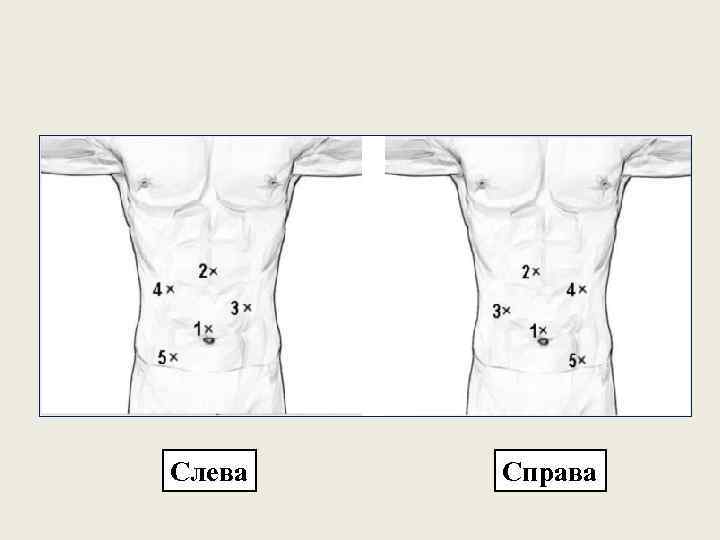

Слева Справа